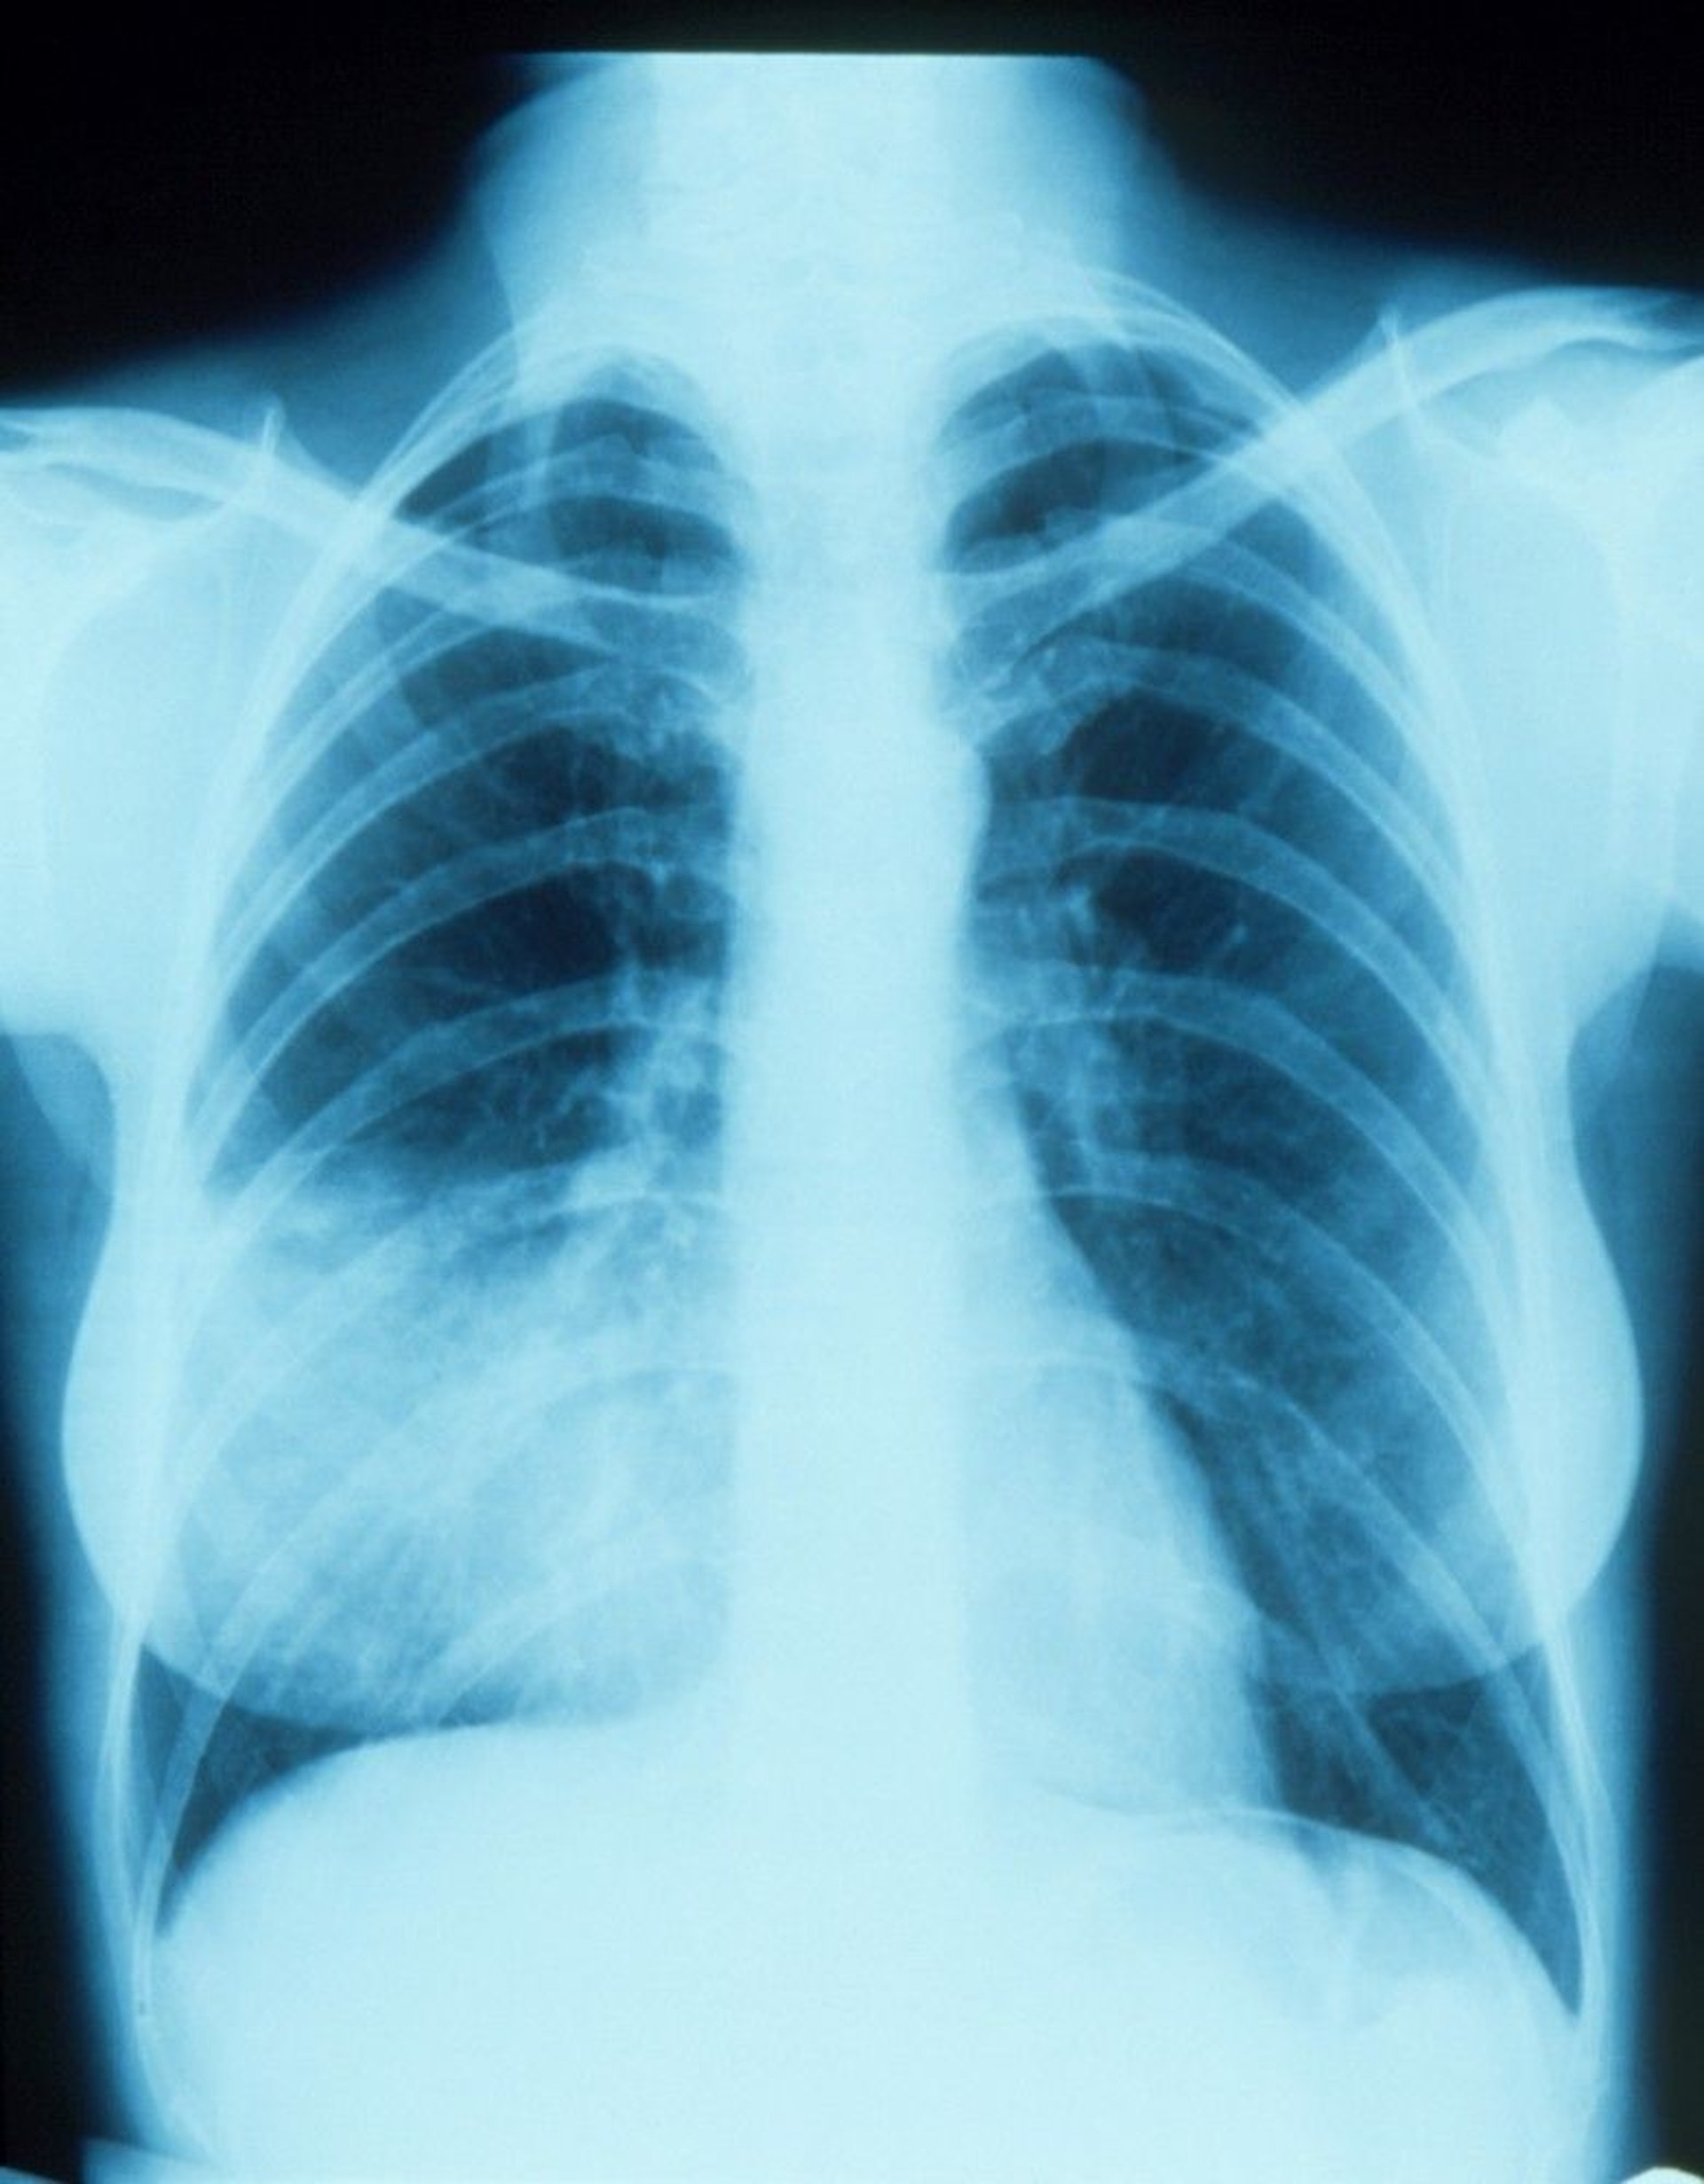

Pneumonia of the Right Middle Lobe With Silhouette Sign

This chest x-ray shows an infiltrate that appears to blend with the right heart border (silhouette sign). The silhouette sign indicates contiguous positioning of the 2 structures that have similar radiodensity; the part of the lung contiguous with the right heart border is the right middle lobe, so that is the part with the infiltrate and pneumonia.